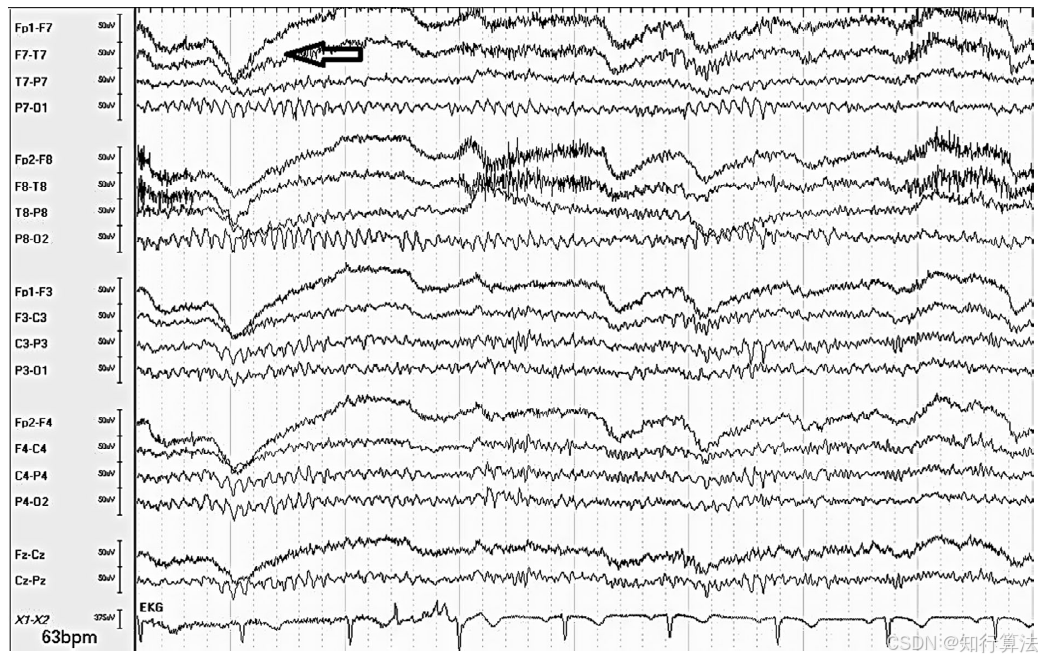

产生原因:头部震颤、腭震颤。

波形特征:

头部震颤:后头部为主的节律性伪迹(图20)。

腭震颤:弥漫性棘-慢波样活动,鼻咽电极明显。

临床意义:可能误认为癫痫发作。

图20:头部震颤伪影(以枕叶为主的有规律震颤)